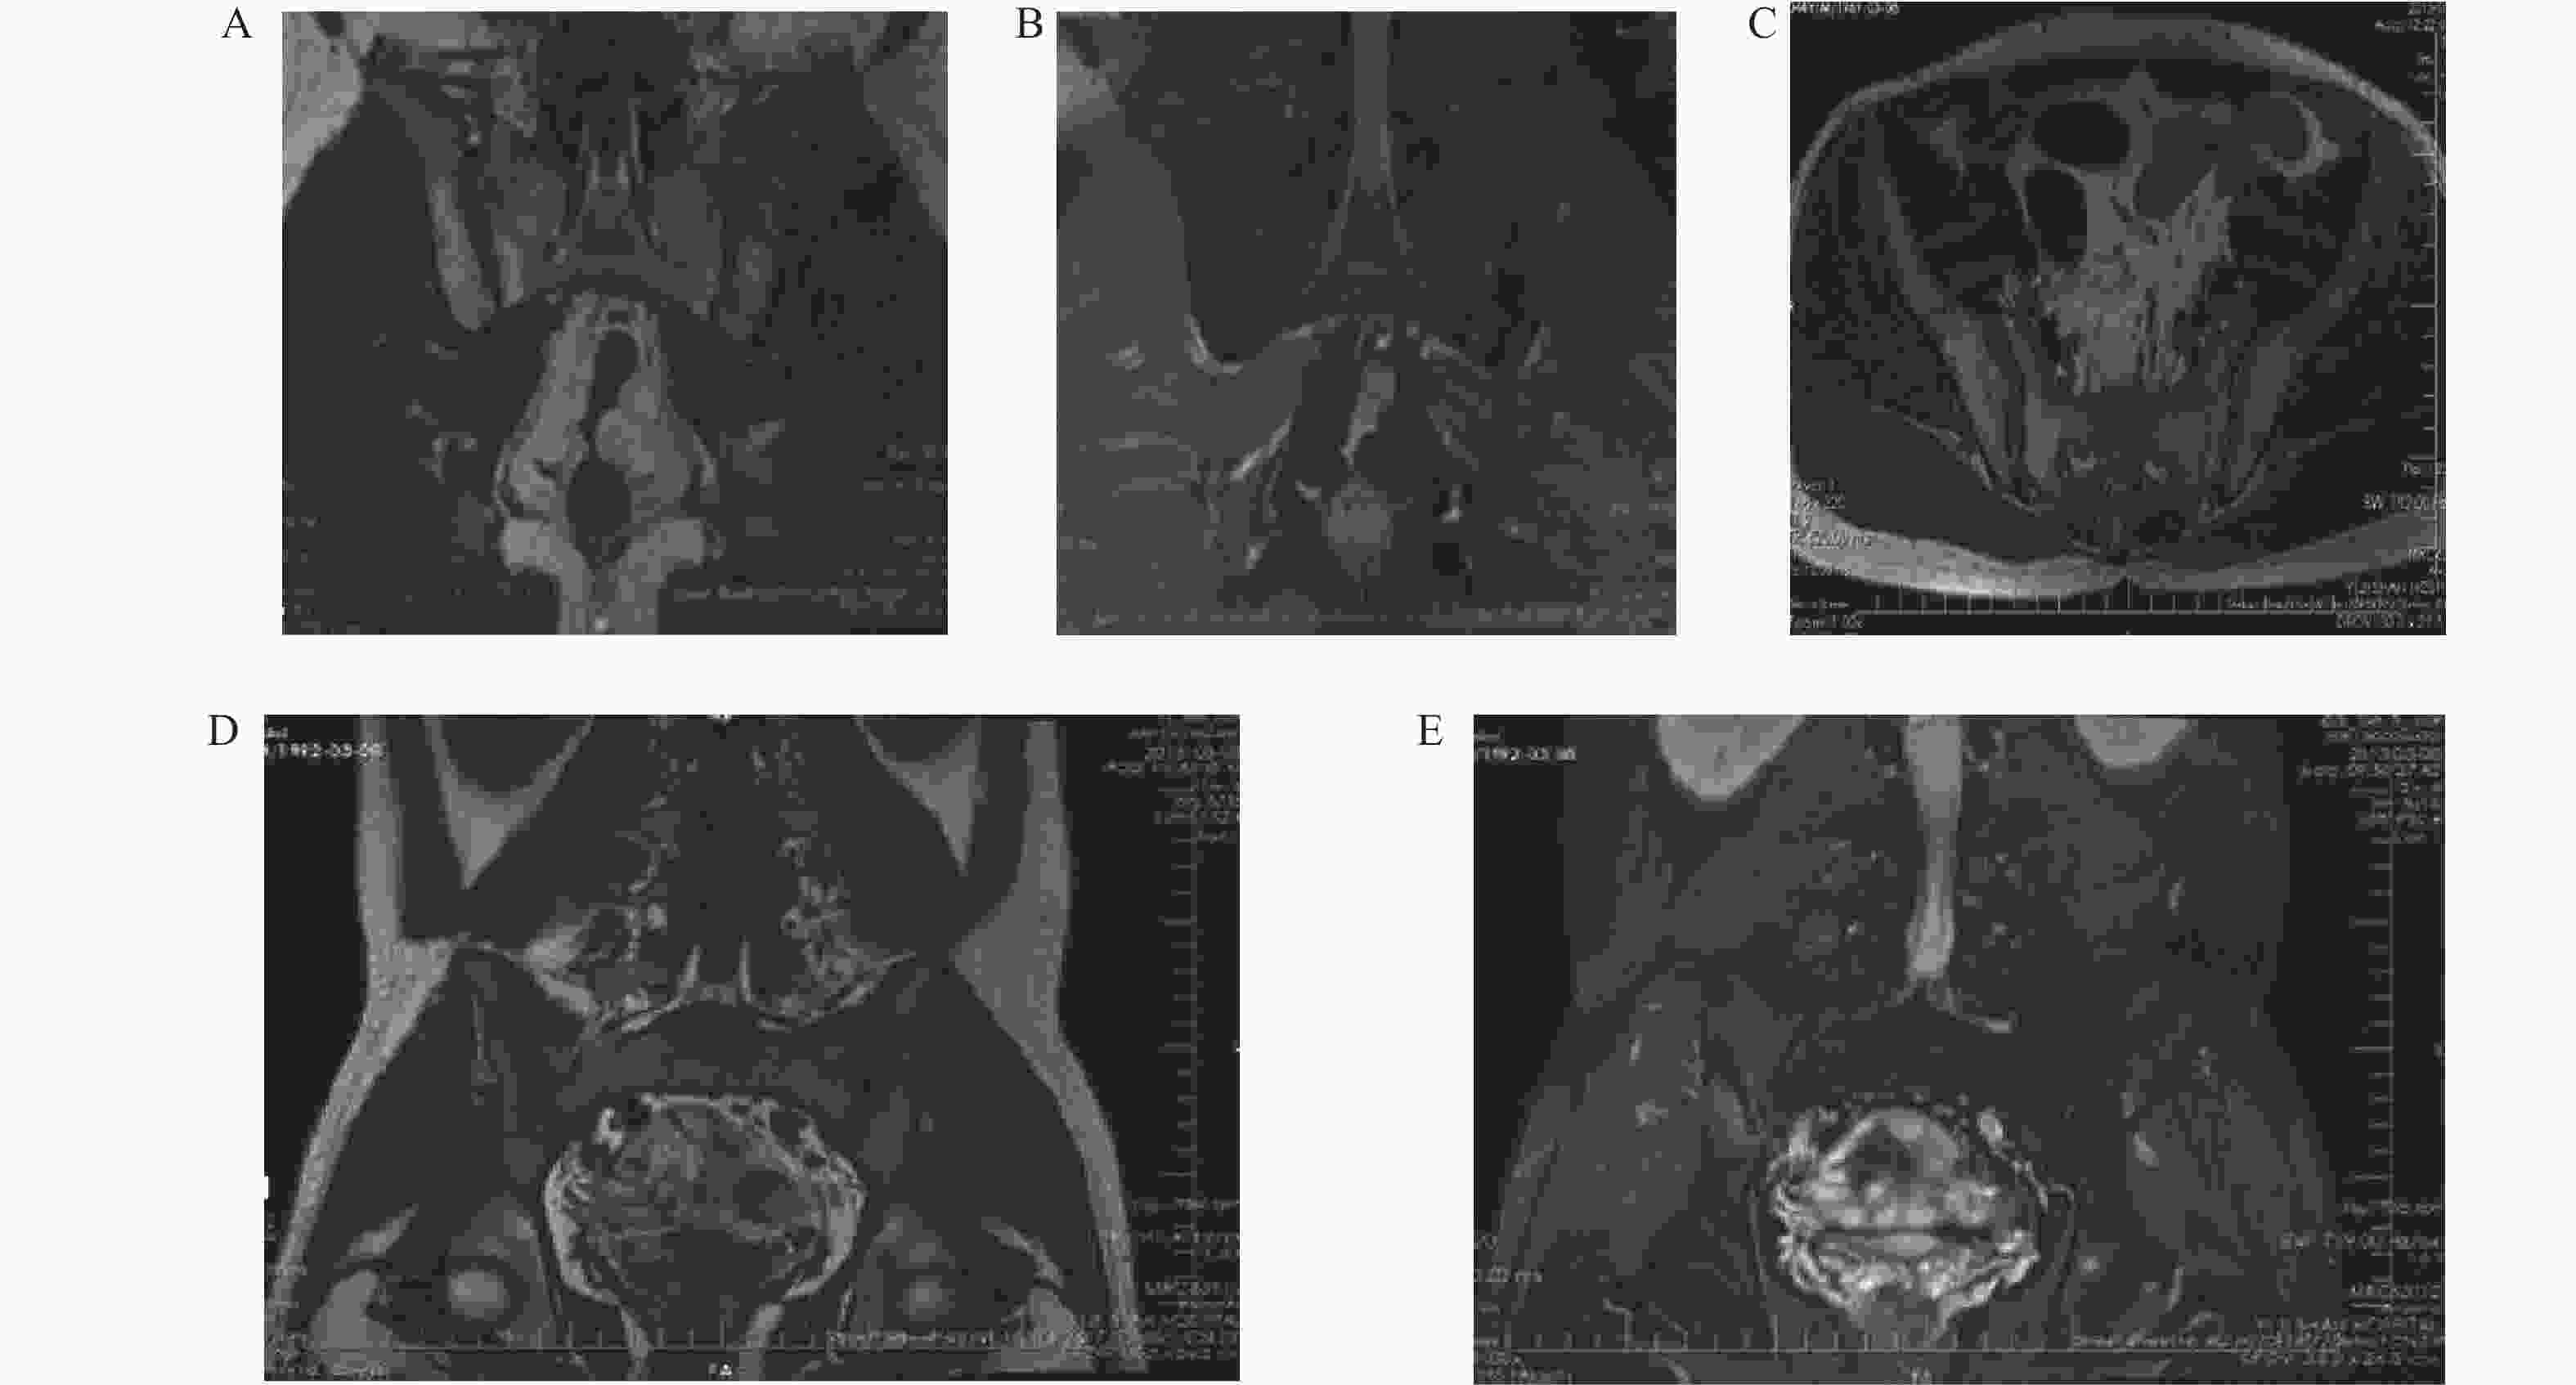

图  2  AS骶髂关节病变MRI表现

A:AS关节面下脂肪沉积,T1WI冠状位骶髂关节面下呈高信号影;B:AS关节面下脂肪沉积,压脂PDWI图呈低信号;C:为右侧骶髂关节软骨破坏,横轴位T1WI图示软骨扭曲、毛糙;D:骨髓水肿,冠状位T1WI低信号;E:骨髓水肿,冠状PDWI高信号。

Figure  2.  MRI manifestations of sacroiliac joint lesions in ankylosing spondylitis